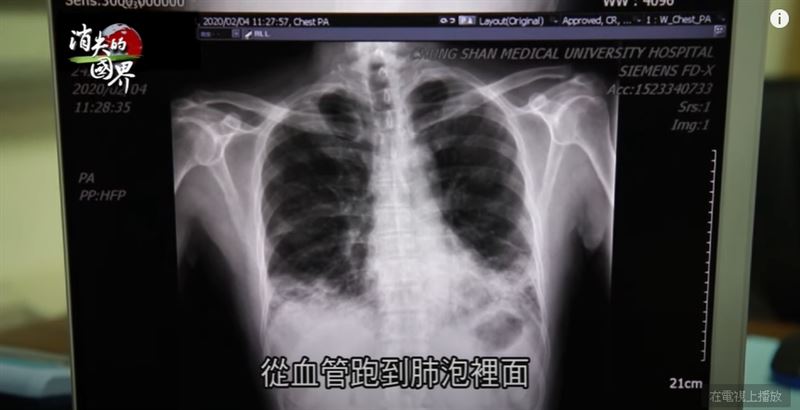

今年六月起,台灣大解封,歐洲、東亞等國,下半年也逐漸開放邊境,但醫療專家擔心,秋冬可能再爆第二波疫情。加上病毒變異性高,新冠病毒的解藥和疫苗研發,還有漫漫長路。